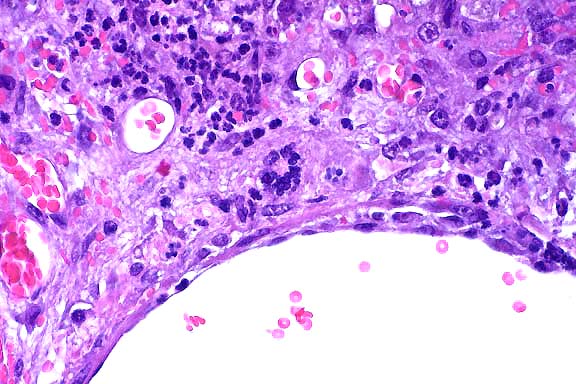

10x

- Case 15-4. Liver. Severe focal to coalescing necrosis

is associated with inflammatory cell infiltration and syncytial

giant cells.

40x

obj

- Case 15-4. Liver. Areas of hepatocellular necrosis

are replaced by necrotic cellular debris, hemorrhage, neutrophils

and occasional clusters of nuclei (hepatocyte syncytium). An

adjacent hepatic vein contains endothelial cell hypertrophy and

hyperplasia.

- AFIP Diagnosis: Liver: Necrosis, random, multifocal

to coalescing, with syncytia and mild neutrophilic inflammation,

CBA/CaJ mouse, rodent.

- Conference participants identified prominent syncytia at

the periphery of necrotic foci within the liver; infrequent endothelial

syncytia are present in some sections. Participants briefly discussed

several potential causes for random hepatic necrosis in the mouse,

including Tyzzer's disease (Clostridium piliforme), salmonellosis,

and mousepox (ectromelia virus). Tyzzer's disease and salmonellosis

do not have syncytial cells as a characteristic microscopic finding.

If present in sections, salmonella organisms may be demonstrated

by tissue Gram stains as short, Gram-negative, bacilli. Necrosis

of Peyer's patches frequently occurs with enteric salmonellosis.

Silver stains, such as the Warthin-Starry, best demonstrate the

bacteria in Tyzzer's disease. They appear as filamentous bacilli

within hepatocytes at the periphery of necrotic areas. In the

liver lesions of mousepox, intracytoplasmic inclusions are evident

in hepatocytes at the periphery of necrotic foci, and syncytial

cells are not present. Cutaneous lesions, splenic necrosis, and

necrosis of lymph nodes and Peyer's patches are often present

in cases of mousepox.